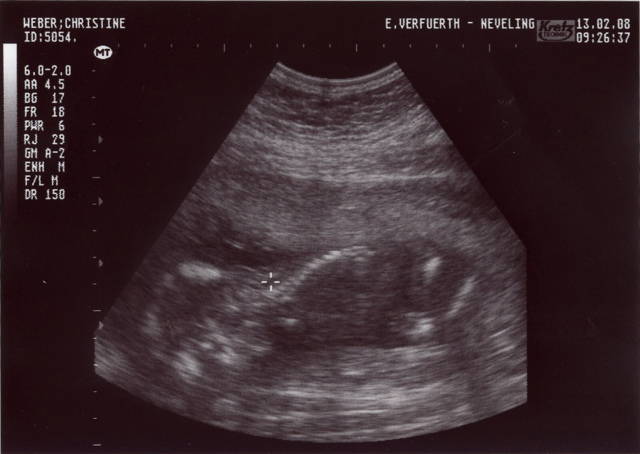

Mama und Papa haben mir freundlicherweise Bilder von meiner Ein-Zimmer-Wohnung zur Verfügung gestellt. Erstellt wurden die mit so einem Ding namens Ultraschall. Ich weiß nur noch, dass ich in den ersten Wochen von dem Teil überhaupt nicht begeistert war und mich immer ganz klein gemacht habe, wenn Mama und Papa schon wieder knippsen wollten. Aber wer lässt sich schon gern freiwillig in seine Privatsphäre schauen?

Ein paar Wochen später konnte man schon meinen Kopf …

… und auch den Rest meines Körpers erkennen.